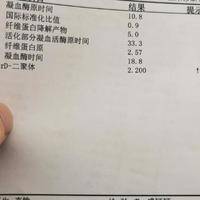

试管移植30周后D二聚体变高是正常孕期变化吗?

问题描述:昨天去做了孕检,试管移植已经30周了还好这期间胎儿都在正常发育。但D二聚体这项检查结果提示数值有稍微变高的迹象,我就有点担心噻,不过,直到检查结束医生都没有说什么,所以我想问问这个情况属于孕期正常变化吗?最佳回答:怀孕期间D二聚体会变高,不过也有可能是感染、血栓或者其他不良妊娠反应所引起。D二聚体是一种血液凝固因子,在体内发挥着重要的作用。当胚胎植入子宫后身体免疫反应可能会导致D二聚体水...